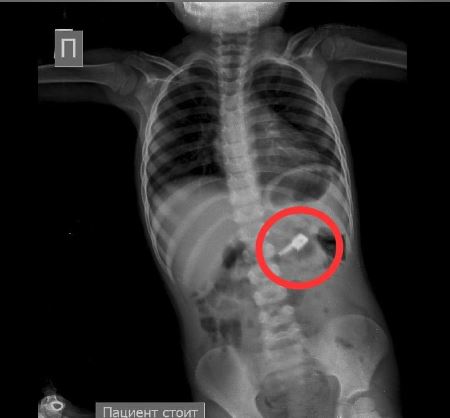

При этом на обзорной рентгенограмме брюшной полости были обнаружены бегунок и, предположительно, две швейные иглы в проекции желудка, сообщает Sputnik Казахстан

При проведении процедуры ЭФГДС из желудка удалена одна игла, бегунок отсутствовал. Ребенка оставили в хирургическом отделении детской больницы под наблюдением специалистов. В результате бегунок со стулом вышел самостоятельно.

— На контрольной R–грамме брюшной полости обнаружены еще 2 иглы в верхнем этапе брюшной полости и 1 игла в проекции таза. Проведена повторная ЭФГДС и удалена игла из желудка. Затем при помощи колоноскопии удалена игла, фиксированная в сигмовидной кишке, — сообщил врач-хирург высшей категории Сейдахмет Чинибеков.